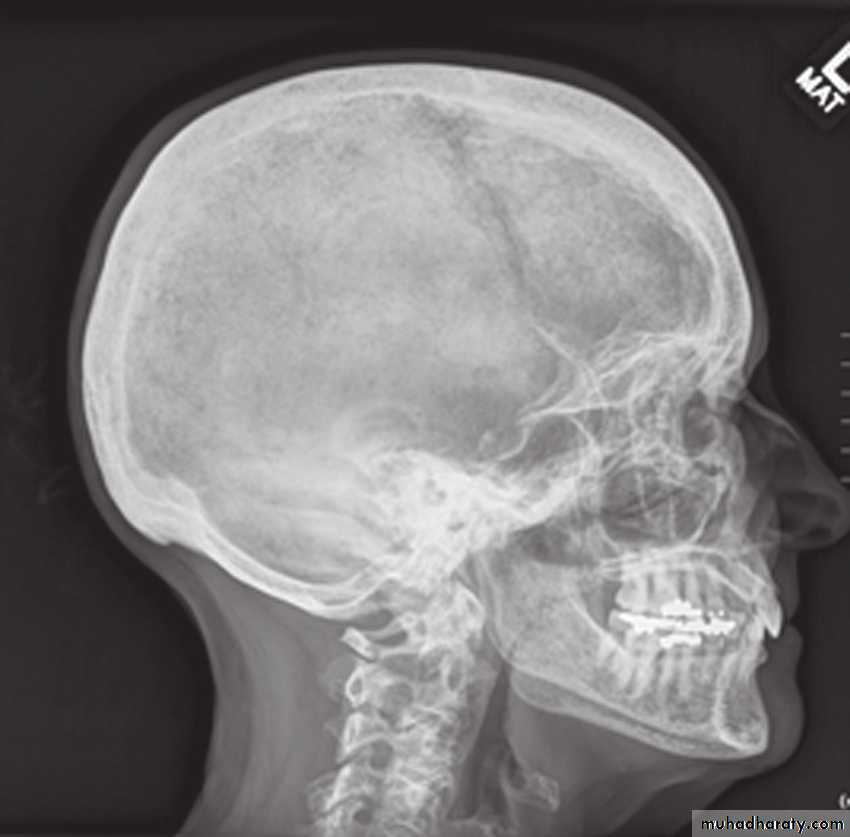

Orthopantomogram

This is essential in all trauma cases where underlying bony injury is suspected.